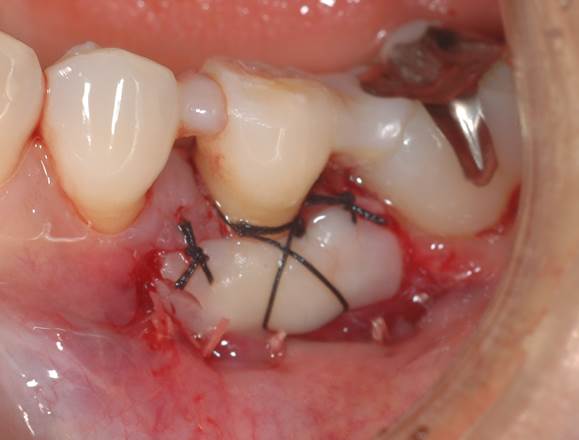

まずはブラッシング指導、次に歯肉上に付着している歯石および歯肉下に付着している歯石の除去を行います。その間に、歯牙の暫間的固定を行っています。そして、付着歯肉獲得のために遊離歯肉移植を行いました。

レントゲンで初診→再評価→術後と歯槽骨の再生が観察されます。

フラップ手術や自家骨移植を予定していましたが、SRP(歯肉縁下歯石の除去)のみで骨再生が生じ、抜歯予定の歯を保存することが出来ました。